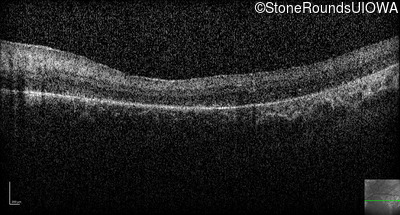

Optical Coherence Tomography - Left -

No Light Perception

Exemplar

Expanded OCT Stack

×